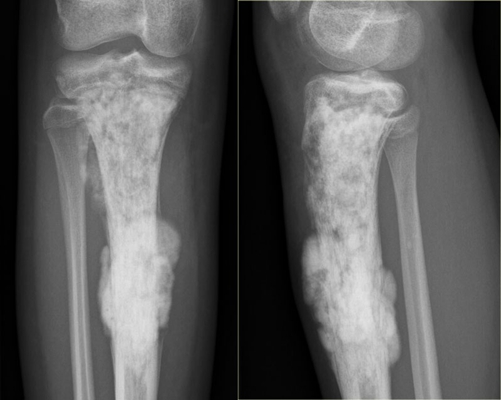

骨癌圖片

骨癌